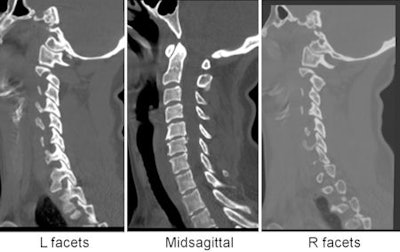

![]() |

| Images of patient involved in a motor vehicle collision, who had head injury in addition to long-bone fractures of the lower legs. She was unable to participate in a reliable clinical exam. Her initial MDCT scan was negative for acute injury. |